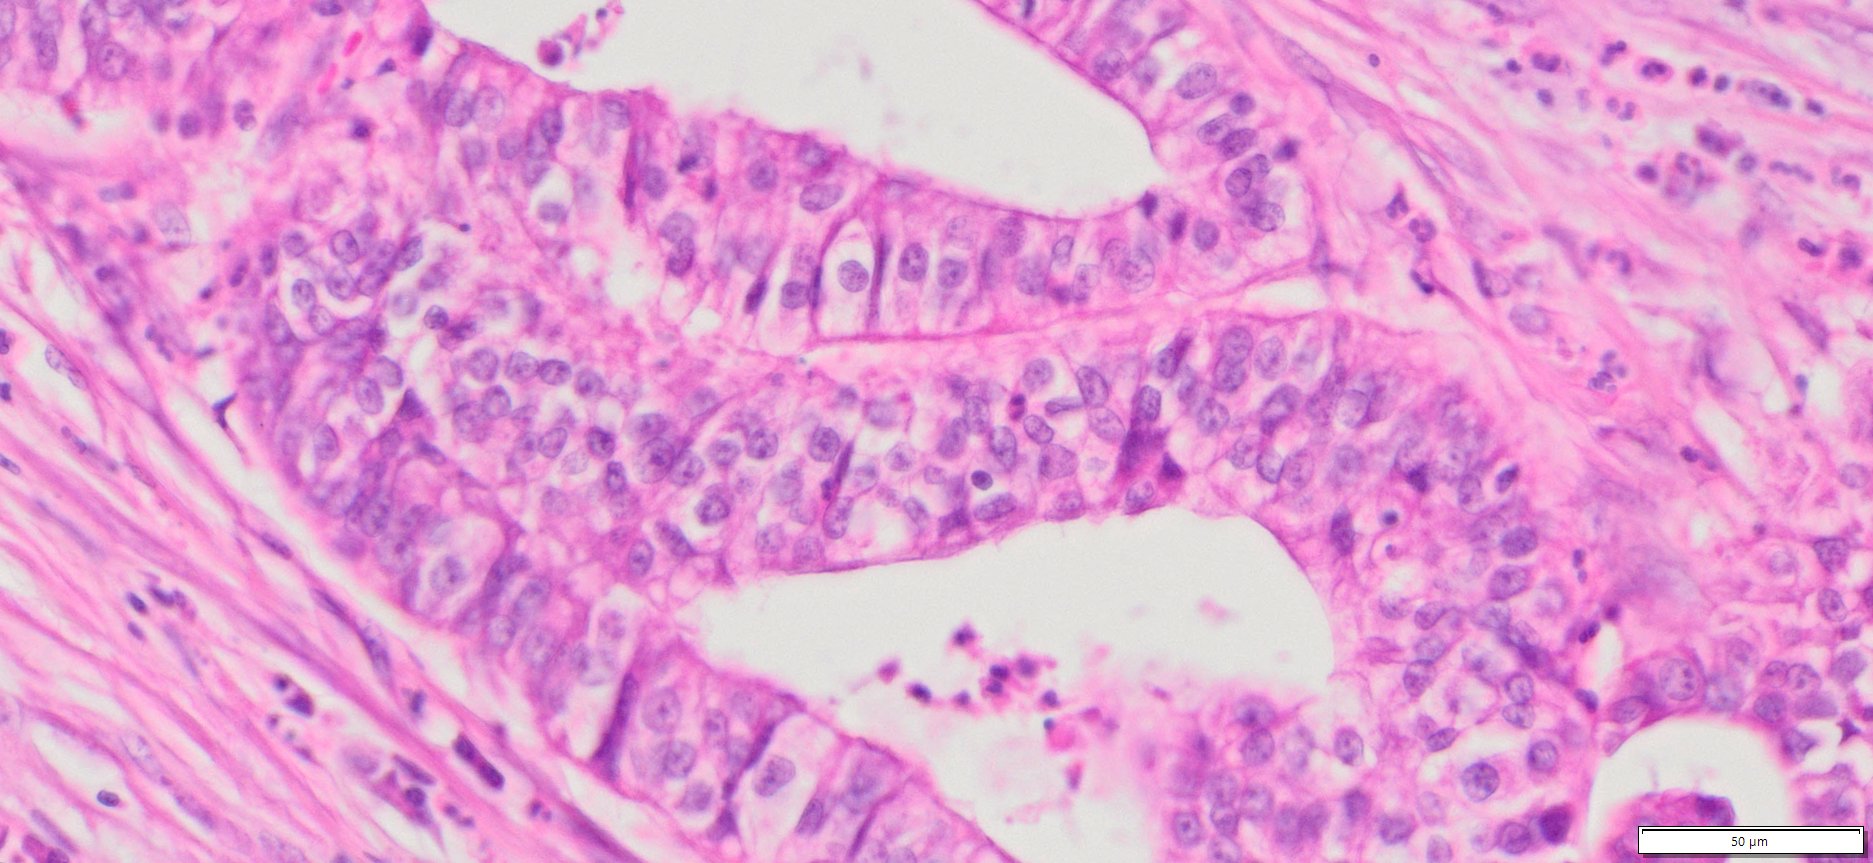

Description

| Tissue | Pathology Diagnosis | Gender/Age (year) | Tissue of Origin | % Tumor area | Tumor Grade | TMN Stage | IHC Data |

| Human Pancreas Cancer | Pancreatic ductal adenocarcinoma | Female/76 | Head of Pancreas | 75% | II | PT2PN1Mx | NA |

Human tissue was fixed in formalin immediately after excision and embedded in paraffin. The tissue sections were 5 µm in thickness and mounted each on positively charged glass slides.